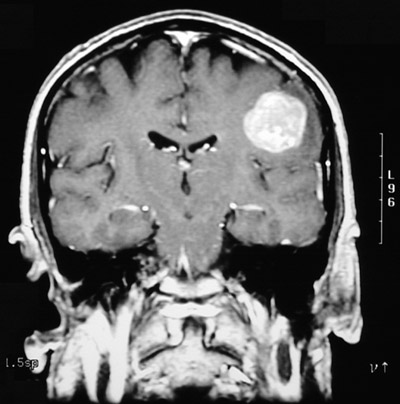

Image 8.1

This T1 weighted post-contrast MRI scan in coronal view demonstrates the lesion. The mass lesion is brightly enhancing and could represent either blood or a neoplasm.